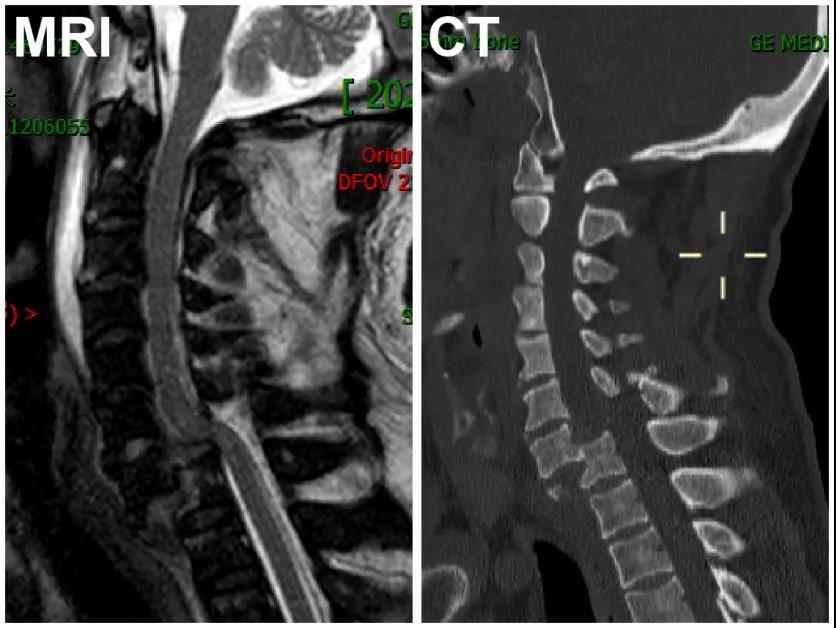

图1、患者入院时的MRI及CT检查显示:C7椎体完全脱位,相应节段脊髓未见明显卡压

影像学的进一步检查显示患者C7椎体完全脱位,其后缘移位至胸椎椎体(T1)前方并形成绞索,但脊髓却未见明显卡压(如图1所示)。这给医生们带来了难题:如何在有效复位固定的同时避免脊髓的二次损伤?